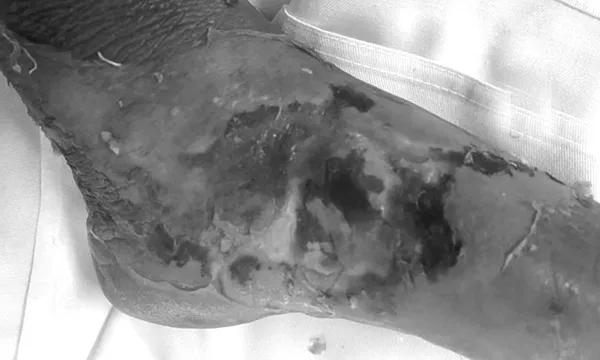

Người đàn ông (53 tuổi, ở Quảng Yên – Quảng Ninh) vô tình bị rắn cắn. Sau khi tự đắp thuốc tại nhà, người đàn ông phải đến bệnh viện Việt Nam - Thụy Điển Uông Bí với vùng chân sưng tấy, nóng rát.

Các bác sĩ đã tiến hành xử trí vết thương: cắt lọc tổ chức hoại tử và điều trị kháng sinh tích cực để kiểm soát nhiễm trùng.

Bệnh viện cảnh báo người dân, việc tự ý điều trị bằng các bài thuốc dân gian chưa được kiểm chứng có thể khiến tình trạng bệnh trở nên nghiêm trọng, thậm chí dẫn đến hoại tử, nhiễm trùng huyết, nguy hiểm tính mạng.